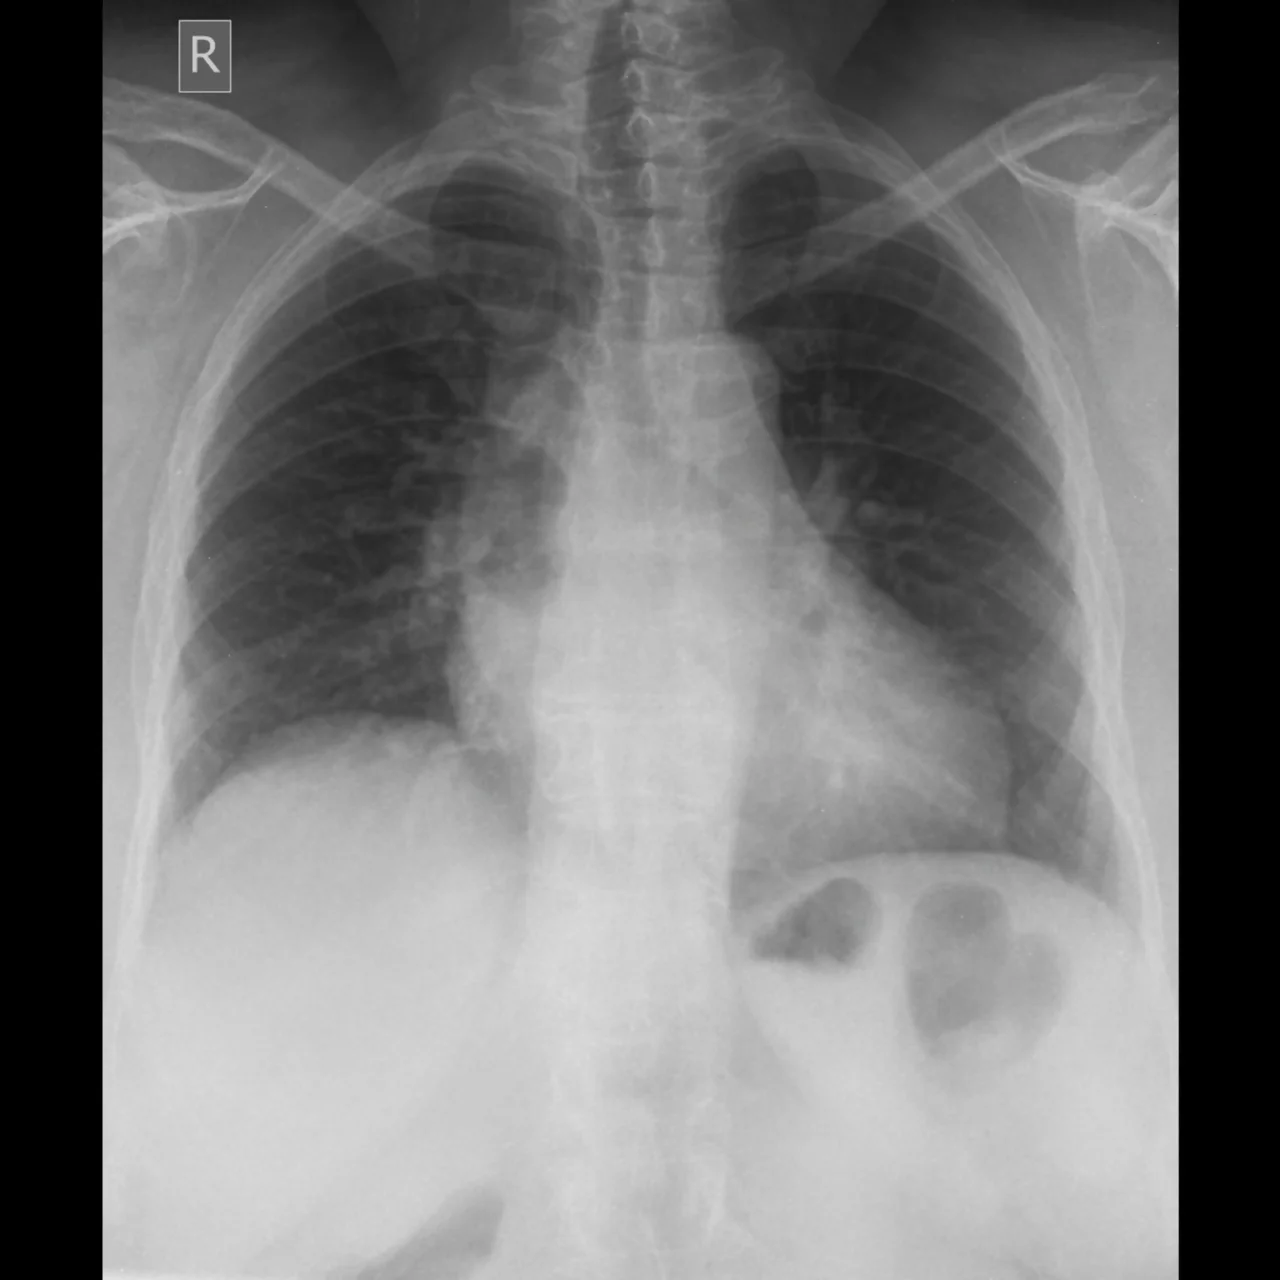

Pero para confirmar el agrandamiento del corazón, se requiere de estudios de imagen como la radiografía de tórax, que es uno de los métodos más utilizados de manera inicial, al permitir ver el tamaño y la forma de la silueta cardíaca.

Radiografía de un paciente que presenta corazón dilatado o cardiomegalia.